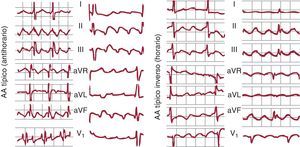

Aleteo auricular típicoEl AA típico es la TAMR más frecuente, y en general se puede identificar por un patrón de ECG muy característico en derivaciones inferiores que, aunque se describe frecuentemente como una onda negativa, es en realidad una ondulación compleja con una fase descendente lenta, seguida de un pequeño descenso rápido (la «onda negativa») y un rápido ascenso que termina en una deflexión positiva, para enlazar de nuevo con el descenso lento del ciclo siguiente (Figura 1, Figura 3, Figura 10). En V1 se pueden registrar deflexiones positivas, bifásicas o a veces negativas.

Figura 10. A la izquierda electrocardiograma en 2 casos de aleteo auricular típico (antihorario), con las típicas ondas multifásicas en II, III y aVF y con deflexiones bifásica y positiva en V1. A la derecha, 2 casos de aleteo auricular típico inverso (horario), con ondas de aspecto positivo en II, III y aVF y el típico patrón de W en V1 (véase el texto para más explicación). AA: aleteo auricular.

En un 90% de los casos, el giro de la activación en el circuito de AA típico es antihorario en una visión oblicua anterior izquierda (descendiendo la AD anterior y ascendiendo la septal). Esta preferencia podría deberse a una mayor facilidad para el bloqueo de la conducción descendente en la AD septal baja, donde el miocardio es de muy escaso grosor y alineamiento irregular. Si una extrasístole se bloquea a este nivel, la conducción del frente de activación descendente por la cara anterior podría reentrar la AD septal a través del istmo cavotricuspídeo (ICT), y así se inicia el giro antihorario. El AA típico inverso (horario) recorre el mismo circuito descendiendo la AD septal y ascendiendo por la AD anterolateral, con la misma línea de bloqueo en la AD posterolateral y el mismo cierre inferior a través de ICT (Figura 7, Figura 10). El patrón de ECG es distinto del AA antihorario, con inscripción en cara inferior de deflexiones positivas melladas en forma de M y en V1 de onda negativa, ancha, mellada en forma de W (Figura 10).